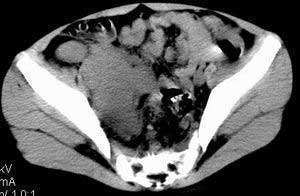

| 患者,男,9岁,因右下腹包块入院,血象不高,不规则发热,常超40度。 平扫: ![]() ![]() ![]() ![]() ![]() ![]() ![]() ![]() ![]() ![]() ![]() ![]() ![]() ![]() ![]() ![]() ![]() ![]() 增强: ![]() ![]() ![]() ![]() ![]() ![]() ![]() ![]() ![]() ![]() ![]() ![]() ![]() ![]() jiajie发言:骶椎右前区不规则软组织肿块,边缘光整,密度均匀,增强后均匀强化,右腹股沟区可见肿大淋巴结,临床有时发热,考虑淋巴瘤,儿童盆腔肿瘤应与神经母细胞瘤和横纹肌肉瘤鉴别。 longzhanghui发言:印象:盆腔右后壁不规则软组织肿块,并向前延伸.似为多个肿块融合,呈中等强化.初步考虑淋巴瘤. 听蝉观竹发言:右侧髂内、外组淋巴结肿大,从其形态和融合的情况看,同意大家意见-----考虑恶性病变,但是9岁男孩还要注意检查睾丸情况,有无隐睾? 常常类似情况是隐睾发生精原细胞瘤淋巴结转移,这个病例也要注意这一点!!! 广东凌发言:大家好,在这里我想说一下个人观点,我建议上传图片的同志能否辛苦一点就是把病史和图片都上传完整一点,比如这个病人的腹膜窗,并且这个病人的肠道的准备也是不怎么好,就从现有的质料看:病灶属于淋巴结肿大当无大的争议,有融合趋势,其内无坏死,边缘强化为主,故考虑:淋巴瘤!建议用腹膜窗看一下和肠道的关系! 阿圣发言:病灶属于淋巴结肿大当无大的争议,有融合趋势,其内无坏死,边缘强化为主,故考虑:淋巴瘤 结果是:淋巴瘤 病例来源:ct762。由宁静致远发布: http://www.radinet.com.cn/forum_view.asp?forum_id=4&view_id=2182 |